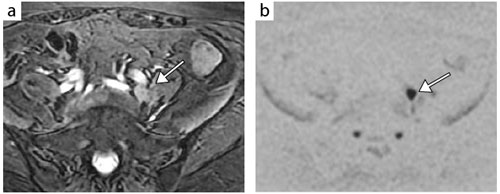

図5 体幹部の拡散強調像:子宮頸がんの腸骨リンパ節転移(再発)

T2強調像(a)にて,左外腸骨動脈近位部の背側に小結節腫瘤を認める(←)。拡散強調像(b,白黒反転表示)で高信号を示している(←)。

18F-FDG-PETで集積があり,転移リンパ節と診断された。拡散強調像は1分17秒の撮像で,歪みのない均一な画像が得られている。